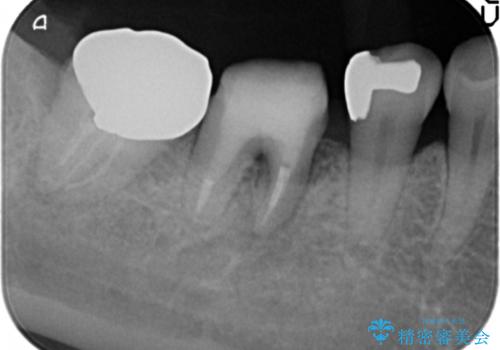

- 他院で根管治療を受け銀歯をかぶせるところまで行ったが、直後より腫れ・痛みが引かず当院へ相談、来院されました。

X線写真検査より根管充填の行われていない根管、視診より歯肉からの排膿路を認め、急性根尖性歯周炎の治療として根管再治療を計画します。

治療途中、マイクロスコープでも根管が追えないほど狭く細くなった根管へと変性しており根管の拡大形成が難しい状況でした。

CTを撮影し少しづつ丁寧に根管を探索することで無事根管再治療を行い、症状がなくなりました。